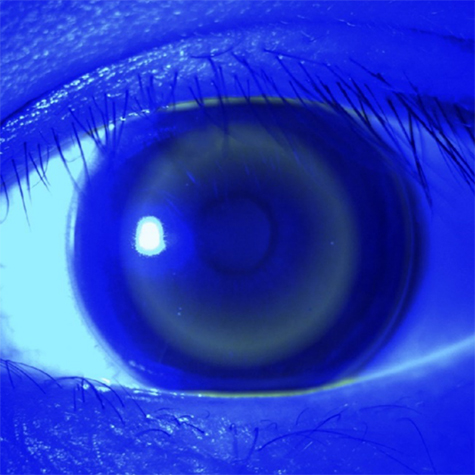

각막굴절교정렌즈. ⓒ제주의소리

광학적 치료로는, “드림렌즈”라고 불리는 각막굴절교정렌즈와 “마이사이트”라는 다초점 소프트렌즈가 있다. 두 방법 모두 근시를 억제하는 기전은 비슷하며, 망막의 중심부에서는 상을 정확하게 맺히게 만들고 주변부에서는 근시처럼 초점이 맺히도록 하여 눈의 길어지는 것을 막는 것인데, 각막굴절교정렌즈는 각막의 굴절률을 변화시켜서, 다초점 소프트렌즈는 렌즈의 초점을 나누어서 이러한 효과를 나타낸다.

각막굴절교정렌즈는 잠잘 때 착용하는 렌즈로, 각막을 일시적으로 평평하게 만들어서 낮 동안 안경을 착용하지 않아도 되는 장점이 있지만, 딱딱한 하드렌즈이기 때문에 이물감이 있을 수 있고 수면시간이 어느 정도 확보가 되어야 하는 불편함이 있다. 다초점 소프트렌즈는 아침에 착용해서 10시간 동안 착용하는 렌즈로 일회용이기 때문에 관리가 편한 장점이 있지만, 렌즈를 뺀 저녁 시간에는 안경을 착용해야 하고 소프트렌즈이므로 심한 난시는 교정하기 어렵다. 두 방법은 각자의 장단점이 있으므로 환아의 굴절 상태와 성향, 상황 등에 맞추어 안과 전문의와 상의하여 결정하는 것이 좋다.